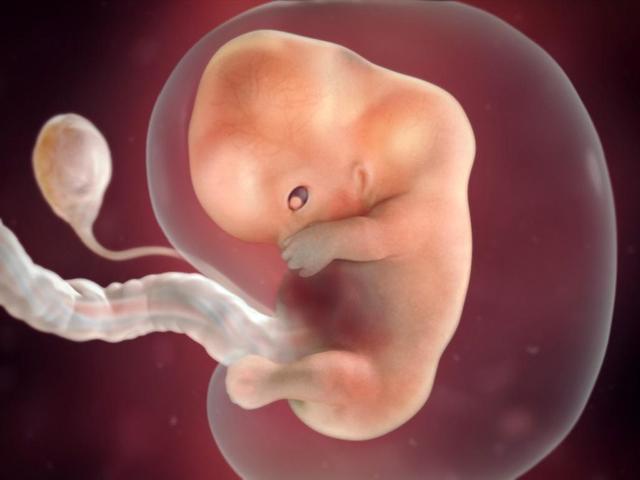

• Week Six

Week Six

The heart is starting to beat . The brain, blood vessles and the spinal cord are begining to form.

Fun Fact: your baby is the size of a rasin.

• Week Seven

Week Seven

The heart is beating with one chamber while organs are begining to grow. The legs and arms are growing and looking like paddles.